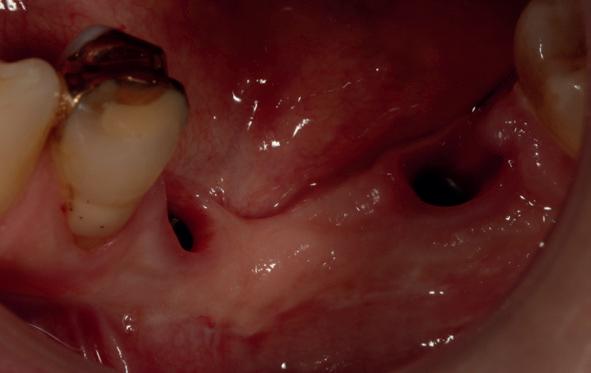

Vervaardigen essix retainer met dummies waarbij er een emergence profile van de 11 en 21 werd gevormd door eivormige dummies 4 mm in de gingiva te plaatsen

• Aanvulling zachte weefsels met de VISTA techniek en een vrij gingivatransplantaat uit het palatum links en direct dragen van de essix retainer

Na 4 weken intra-orale scan voor de etsbrug en kleurbepaling bij de technicus

16. Creëren van een duidelijke indeuking in de mucosa voor emergence profile

17. Genezing van het palatum